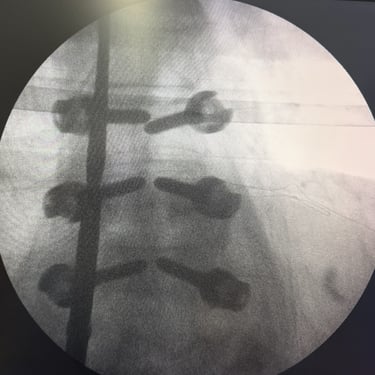

🧠Listesis Lumbar L5–S1 por Fractura Ístmica: Estabilización con FTP y TLIF.

La listesis L5–S1 por fractura ístmica causa inestabilidad y dolor. El tratamiento quirúrgico con FTP y TLIF permite descompresión neural y estabilización vertebral, mejorando la función y calidad de vida.